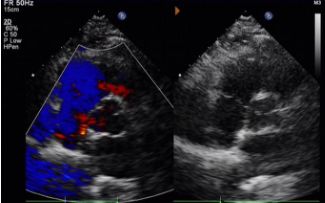

Today, we share a remarkable case highlighting 1-year post-op outcomes of MemoSorb in treating a complex long-tunnel PFO (12mm length, 1.4mm width), with a focus on serial echocardiographic evidence of device degradation and clinical symptom resolution.

Key Follow-Up Imaging Findings

Day 1 to 9 Months:

No residual shunt observed.

Gradual reduction in device echogenicity.